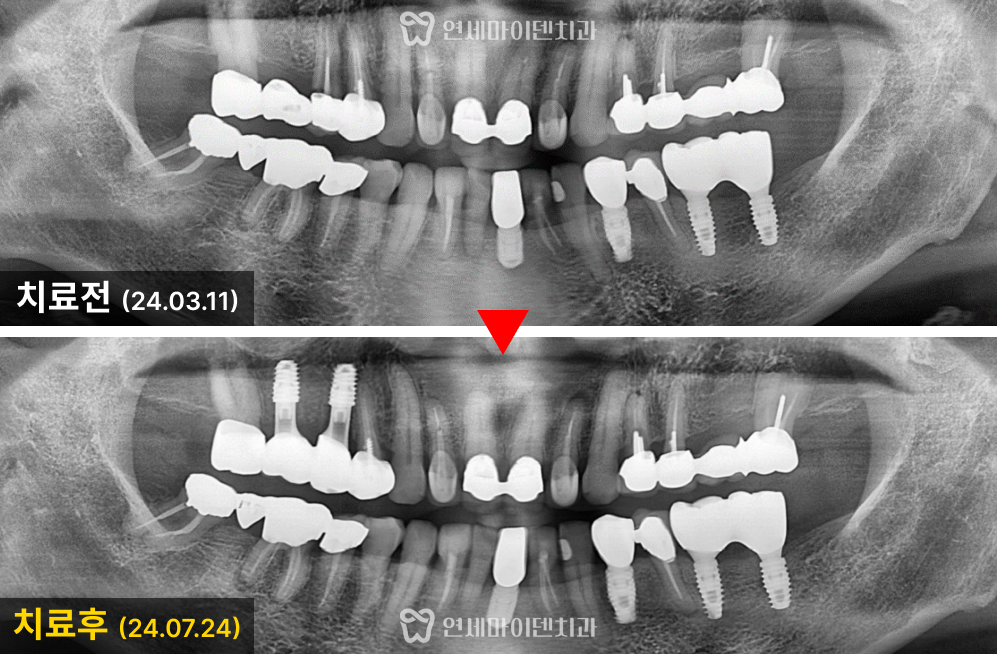

정확한 치료 계획 수립을 위해

3D 네비게이션 CT를 촬영하였습니다.

#15번 치아는 뼈가 상당히 녹아 있었지만

하방에 건강한 뼈가 남아있는 것을 확인했고

임플란트 식립이 가능하다고 판단했습니다.

추가로, 예전에 발치했던 #16번 부위는 상악동과 인접해 있었기 때문에

상악동 거상술과 임플란트를 병행해야 했습니다.

전반적으로 두 부위 모두 임플란트 식립이 가능하다고 판단했고

브릿지를 제거한 뒤 발치 즉시 임플란트를 진행하기로 했습니다.

식립 후 3개월까지 회복을 기다린 후

2차 수술과 최종 보철물까지 안정적으로 완성하였습니다.

브릿지의 가장 끝 #17번 치아는 충치 치료 후

개별적으로 관리할 수 있도록

크라운을 씌워 마무리하였습니다.